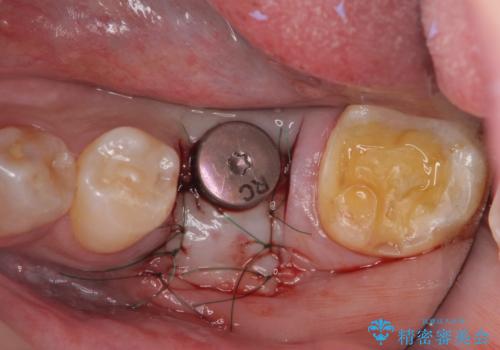

強い噛み合わせによる歯牙破折後のインプラント治療

ブリッジや入れ歯といった周囲の歯の負担を増やす方法ではなく、より強大な咬合力にしっかりと耐え噛むことのできるインプラントを用いた機能回復を計画します。

今回の治療では、周囲の歯に負担を増やし破折リスクを高めるブリッジや入れ歯ではなくインプラント治療を選択しました。

- 外科手術のため、術後に痛みや腫れ、違和感を伴います